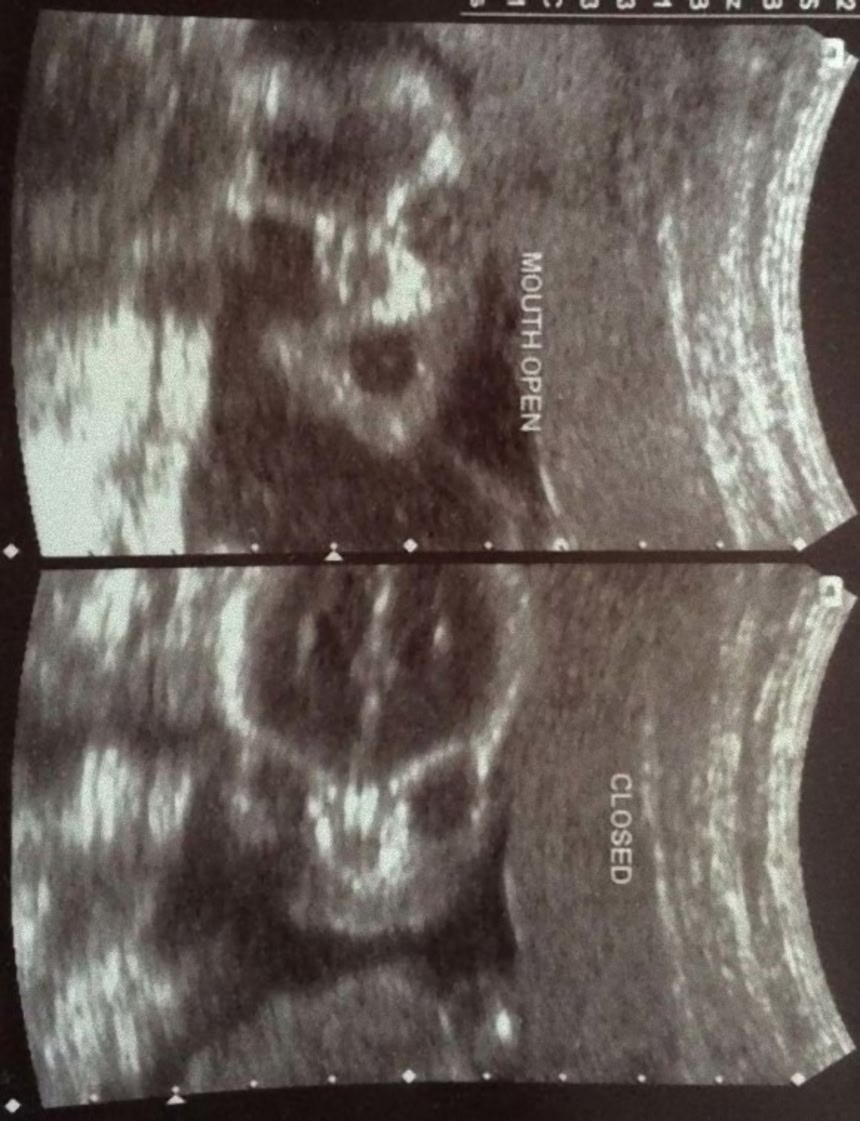

人間の脳は、3つの点が集まった図形を人の顔と見るようにプログラムされているようにできている。これはシミュラクラ現象と呼ばれるものなのだが、モノクロで撮影された胎児の超音波写真は、見方によってはホラーとしか言えない悪夢的光景が潜んでいるようなんだ。

これらの超音波写真は、親御さんがネット上で公開したもので、見方によっては腹にやばいものが宿っているように見えるものだ。

ロールシャッハ・テストじゃないけれど、人によってはまったく違ったものが見えてくるかもしれない。